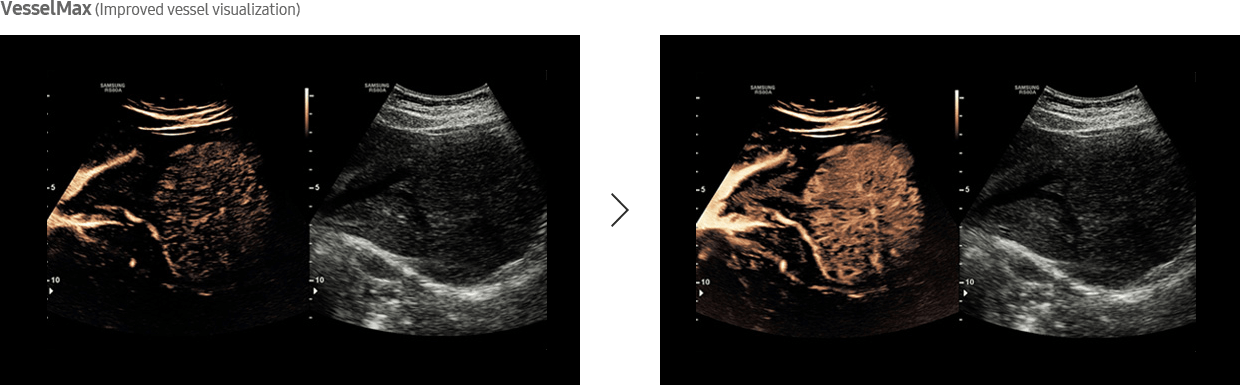

Designed for Advanced Lesion Diagnosis

CEUS+ technology, when stimulated with low MI frequencies, generate oscillating microbubbles that reflect both basic frequencies and harmonic signals. In addition, VesselMax and FlowMax allow for a clear visualization of vessels and blood flow so that you can form an informed, reliable diagnosis with confidence